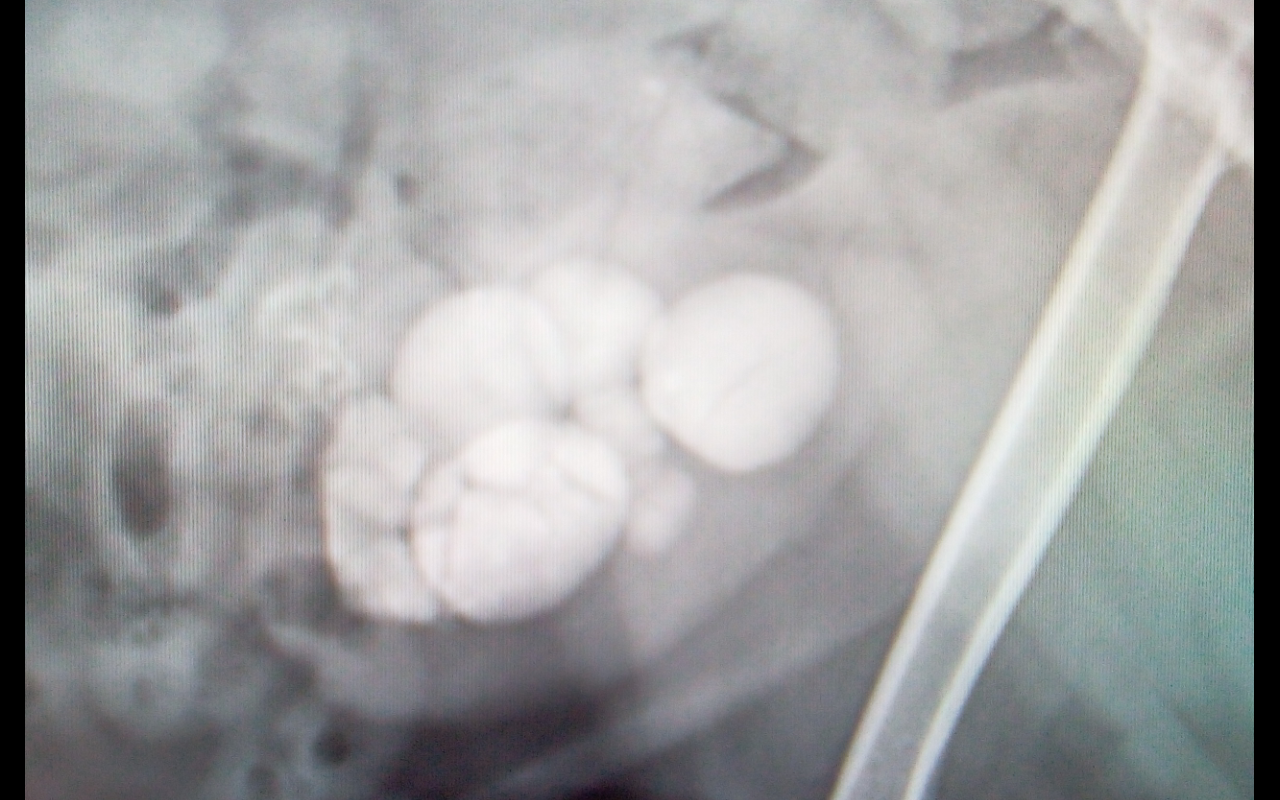

Now Porsche needs your help and I need to ask my community to ensure that it happens, and happens quickly. Porsche suffered a urinary tract infection recently which revealed an underlying problem which has likely been there for a while. She has been diagnosed with a bladder full of almost quail egg sized mineral rocks, found by X-ray. They are too numerous to break up and alternative remedies were ineffective. I made dietary changes. The risk of cleaving one of these stones into pieces and getting stuck in her urethra could be life threatening. Her situation is now urgent, as she has a THIRD round of urinary urgencies and infection. Porsche is a very viable dog and serves to save the lives of many other dogs in my Florida County by training after I rescue. Our County Animal Control has a 42% kill rate so dogs with skills like Porsche are a key part of keeping some alive to be rescued just like she was.